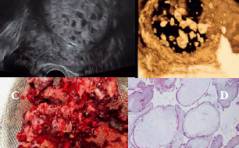

Der spezielle Fall - Ein unkonventioneller Adnexbefund

Eine 61-jährige Patientin stellt sich wegen diffuser rezidivierender Unterbauchbeschwerden beim niedergelassenen Frauenarzt vor. Ultrasonographisch zeigt sich ein zystischer Adnexbefund. Zu-nächst wird die Verlaufskontrolle vereinbart. Da der Befund ... PDF Dokument